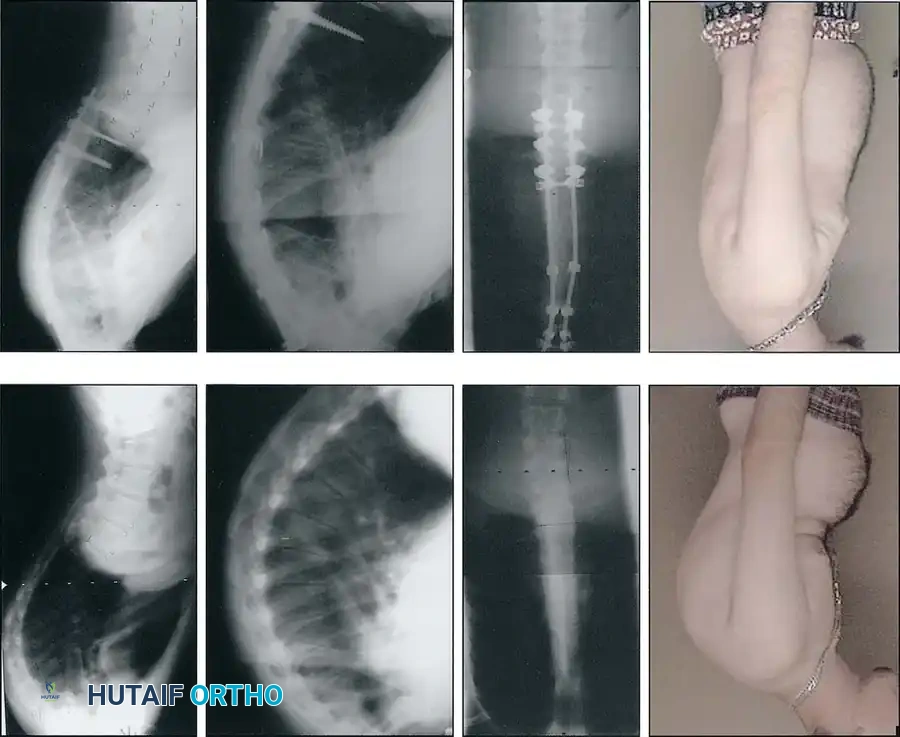

Physical examination reveals a sharp, angular thoracic or thoracolumbar kyphosis accompanied by compensatory cervical and lumbar hyperlordosis.

Crucially, the kyphosis is rigid. During the Adams forward bending test, the deformity becomes more pronounced. When the patient is evaluated using the prone extension test, the structural kyphosis fails to correct, differentiating it from flexible postural kyphosis.

Rigid Scheuermann kyphosis failing to correct on prone extension.

Flexible postural kyphosis demonstrating correction.

Clinical presentation of severe thoracic kyphosis.

Clinical presentation demonstrating compensatory lumbar hyperlordosis.

Postoperative Radiographic Outcomes

Successful surgical intervention yields dramatic restoration of sagittal balance and correction of the deformity.

Postoperative AP radiograph demonstrating a well-aligned posterior pedicle screw construct.

Postoperative lateral radiograph showing excellent restoration of thoracic kyphosis and sagittal balance.

Postoperative AP radiograph of an extended construct.

Postoperative lateral radiograph demonstrating correction of a severe thoracolumbar curve.

Long-term follow-up lateral radiograph showing solid arthrodesis and maintenance of correction.